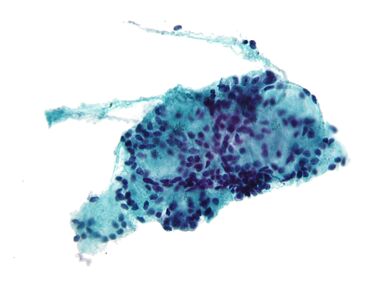

الخزعة بالإبرة (إنگليزية: Fine-needle aspiration، اختصاراً FNA)،هو إجراء تشخيصي يُستخدم لفحص الكتل. في هذه التقنية ، يتم إدخال إبرة مجوفة رفيعة (مقياس 23-25 (قطر خارجي 0.52 إلى 0.64 مم)) في الكتلة لأخذ عينات من الخلايا التي يتم فحصها تحت المجهر (خزعة) بعد تلطيخها.. يُطلق على أخذ العينات والخزعة معًا اسم خزعة الإبرة الرفيعة (FNAB) أو ٍسيتولوجيا الخزعة بالإبرة الدقيقة ( FNAC ) (وهذا الأخير للتأكيد على أن أي خزعة بالرشف تتضمن علم أمراض الخلايا ، وليس أمراض الأنسجة ). خزعات الإبرة الدقيقة هي إجراءات جراحية بسيطة وآمنة للغاية. في كثير من الأحيان ، يمكن تجنب الخزعة الجراحية الكبرى (الاستئصالية أو المفتوحة) عن طريق إجراء خزعة بالإبرة بدلاً من ذلك ، مما يلغي الحاجة إلى الاستشفاء. في عام 1981 ، تم إجراء أول خزعة رشف بإبرة رفيعة في الولايات المتحدة في مركز موسى بن ميمون الطبي.[1] اليوم ، يستخدم هذا الإجراء على نطاق واسع في تشخيص أمراض السرطان والالتهابات.